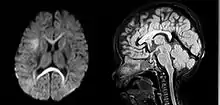

| An MRI of a patient with benign familial macrocephaly (male with head circumference > 60 cm) | |